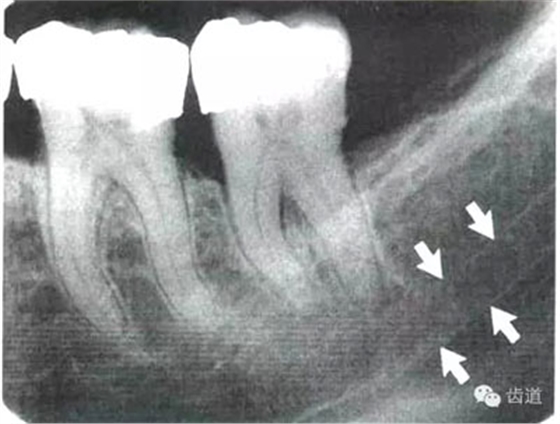

5)下頜管:

位于磨牙牙根尖下方,呈寬約為0.4cm凹面向下邊緣整齊的帶狀密度低的影像,其兩側(cè)有密度高的線條狀影像,為下頜管骨密質(zhì)